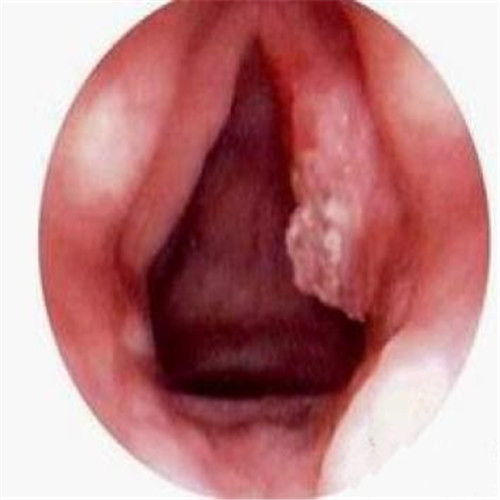

呼吸道感染一側潰爛

呼吸道感染口腔內部發炎

呼吸道感染兩側發炎